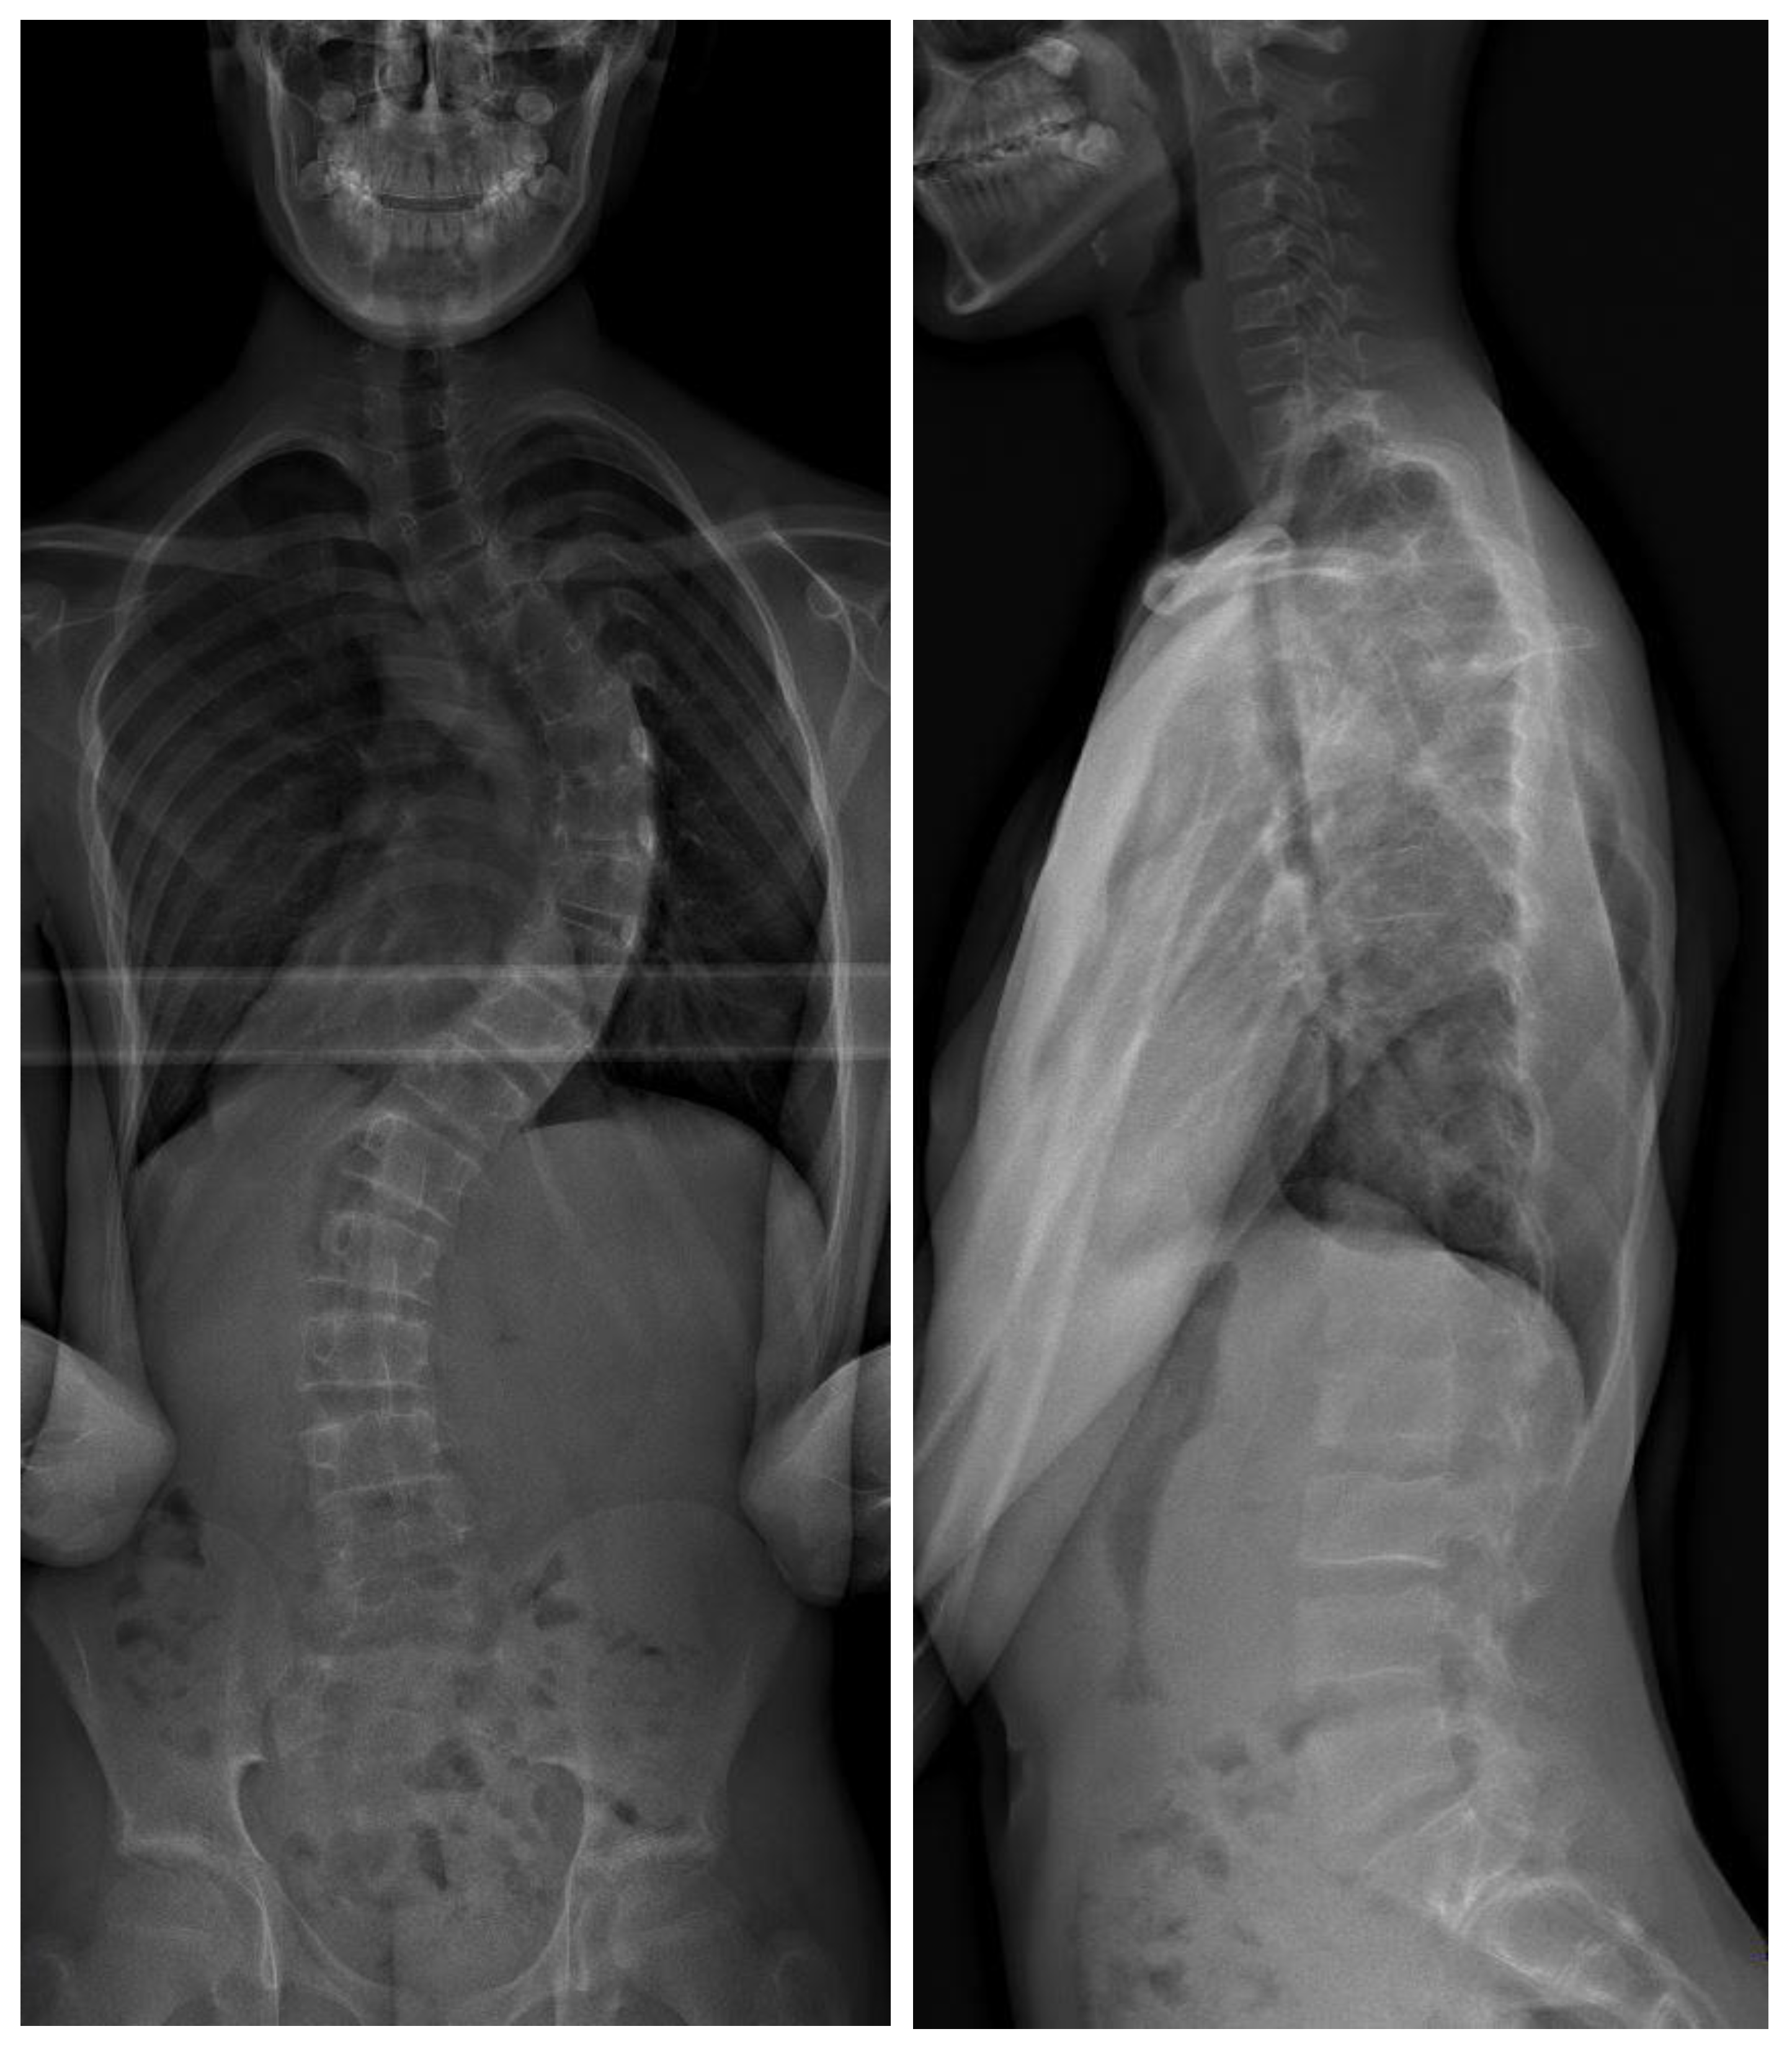

Figure 1.

Preoperative biplanar radiograph of a 15-year-old patient with 62° thoracic scoliosis (Lenke I).